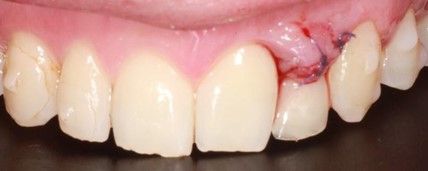

Se presenta un paciente varón de 34 años de edad, no fumador y sin antecedentes médico-quirúrgicos de interés (ASA I), que acudió a la consulta demandando una mejora en la estética de su sonrisa.

El paciente presentaba una agenesia congénita en el incisivo lateral superior izquierdo que había sido tratada previamente con ortodoncia para cerrar dicho espacio.

Tras el examen intraoral del paciente y el estudio radiográfico, se plantea la opción de tratamiento de abrir nuevamente el espacio mediante ortodoncia para rehabilitar la ausencia con un implante de circona, asegurando la estética que demandaba el paciente.